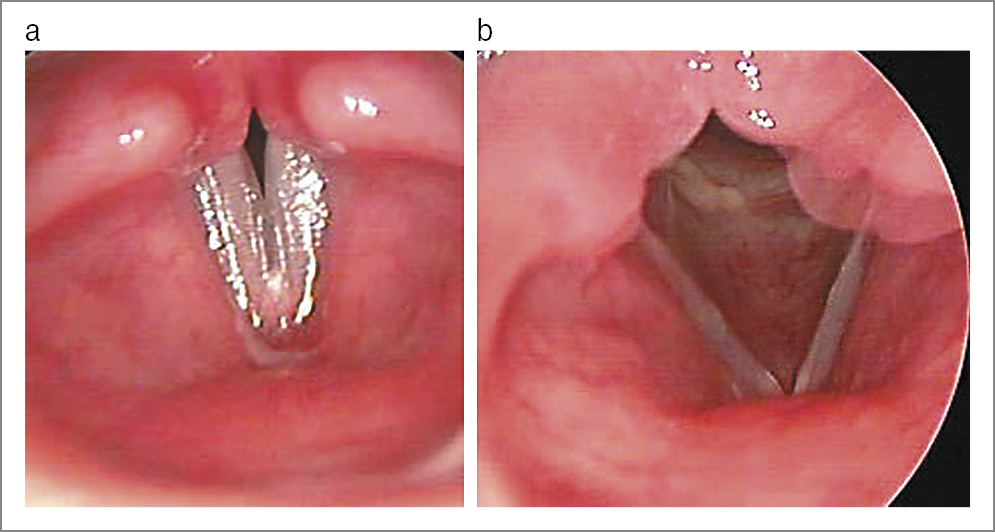

Голос пациентов с бороздками голосовых складок являлся тусклым, отсутствовали звонкость и модуляции. При видеоэндоскопическом исследовании бороздка представляла тонкое или более широкое продольное углубление (ступеньку) на медиальном крае голосовой складки (рис. 1).

Рис. 1. Девочка А., 6 лет. Бороздка правой голосовой складки, узелок левой голосовой складки (дыхание).

У 17 (20%) детей бороздки занимали всю длину голосовой складки, а в 3 (3%) случаях ограничивались частью голосовой складки. Бороздку правой голосовой складки диагностировали у 6 (7%), а левой – у 8 (9%) детей.

Односторонняя локализация патологического процесса присутствовала в 14 (16%) случаях, а двусторонняя – у 6 (7%) детей (рис. 2).

Рис. 2. Мальчик П., 11 лет. Двусторонние бороздки голосовых складок (дыхание).

Оценка видеостробоскопической картины показала, что у всех пациентов колебания асимметричные, нерегулярные, амплитуда уменьшена, слизистая волна отсутствовала или останавливалась на бороздке, фаза контакта как в головном, так и грудном регистре отсутствовала.

Двусторонние бороздки необходимо дифференцировать с функциональной дисфонией по гипотонусному типу. Для обоих заболеваний характерна овальная или треугольная фонационная щель. Однако правильно интерпретировать клиническую картину можно только после осмотра гортани при фонации и в момент входа, когда голосовые складки максимально отведены и натянуты. На противоположной голосовой складке с бороздкой у всех пациентов обнаружили различной выраженности патологические изменения: брюшковидную гипертрофию или отек свободного края, а также полип, узелки, кисту. У 4 (5%) детей с односторонней локализацией бороздки в фонации принимали участие вестибулярные складки. Они находились в состоянии гиперфункции.

У 15-летней пациентки с двусторонними бороздками на фоне длительной подготовки к поступлению в музыкальный колледж выявлена гипертрофия верхней поверхности слизистой оболочки, а над бороздками образовались кисты (рис. 3).

Рис. 3. Девочка А., 15 лет: а – двусторонние бороздки голосовых складок; b – двусторонние кисты голосовых складок заполняют бороздки (видеоэндостробоскопия); c – двусторонние кисты голосовых складок заполняют бороздки (аутофлюоресцентная эндоскопия).

Перечисленные изменения следует расценивать как компенсаторно-приспособительные. Их появлению способствовала работа голосовых складок в условиях форсированного голосоведения. Благодаря этим образованиям голосовые складки максимально приближались друг к другу, голосовая щель уменьшалась, что значительно облегчало голосовую подачу.